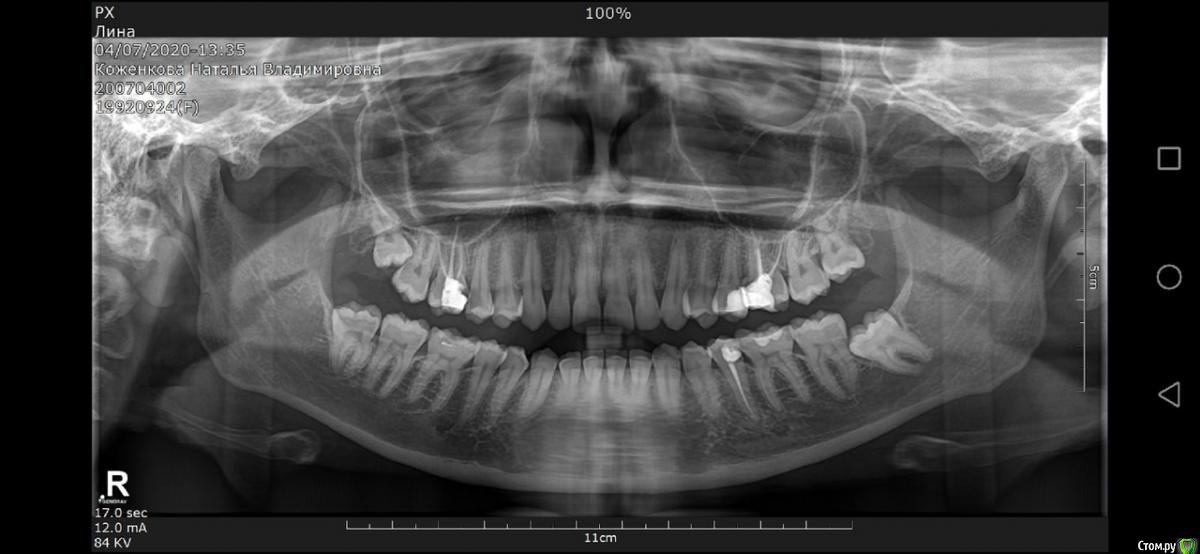

Natkova3 Опубликовано 23 июля, 2020 Поделиться Опубликовано 23 июля, 2020 (изменено) Здравствуйте. Хрустит челюсть уже 2-3 года (может и больше) особо не беспокоила. Последний год вызывает дискомфорт, особенно при пении. При широком открывании рта ощущение поэтапного открывания челюсти. Так же сводит мыщцы при смехе, широкой улыбке. Периодически ощущается усталость (работаю на телефоне, говорю много) 6 июня - упала, ударилась головой (левой частью затылка) сотрясения не было, но затылок продолжал болеть. 1 июля - заболела шея и усилились головные боли 2 июля – опух язык и стало трудно глотать (ощущения, как при аллергии)3-4июля - сильно зажало челюсть, рот открывался на палец, говорить нормально не получалось5 июля - невропатолог прописал мидокалм и кетопрофен, успокоительное и мягкий воротник на 15-20 минут. Назначил обследования шеи и головы, а так же консультацию челюстно-лицевого хирурга.19 июля - спазм прошел, лекарства помогли и начала нормально разговаривать.Лечение невропатолога мне помогло прийти в себя. Но, мне не могут назначить полноценное лечение шейного отдела (зажаты сосуды), пока мне хотя бы что то не скажут по проблеме с челюстью. Проблема в том, что никто из хирургов мне ничего конкретно сказать не может, перекидывают меня с телефона на телефон. Один говорит – необходимо спасать сустав, надо шину и уколы ботокса для разжатия мышц, стоить будет 200к;Другой – пей нимесил и аркоксию, тут ничего серьезного я не верю мрт;Третий – ну еще года 2-3 так можешь проходить, потом хирургическое вмешательство;Четвертый – ой, это всё зубы мудрости.Да и прикус надо менять В итоге я до сих в поиске нужного доктора. И не понимаю, что за диагноз.МРТ и панорамный снимок, прикладываю ниже. На данный момент:- широко рот открыть уже могу, но адский дискомфорт и поэтому стараюсь не открывать так- хруст с левой стороны при зевании (не широком),- чувствую усталость в мышцах лица (немеет при улыбке, разговорах).- при малейшем стрессе снова сводит челюсть.- при прогулке больше часа, начинает болеть шея и челюсть.- зубы могу свести вместе, но чувствуется дрожь Пью лекарства: Мидокалм, Кетопрофен Дуо, УспокоительныеЗаписана на прием к челюстно-лицевому хирургу в ЧЛХ ЦНИИ только на 4 августаВозраст - 27 лет Помогите разобраться с диагнозом. Изменено 23 июля, 2020 пользователем Natkova3 Ссылка на комментарий